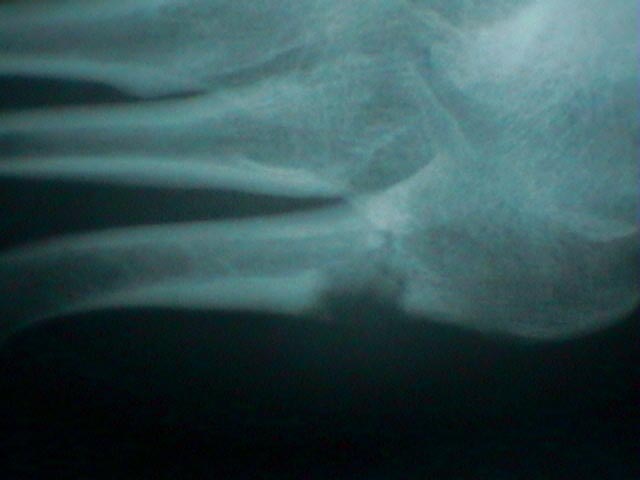

Radiographs

- in the hand look for oval periarticular erosions;

- multiple erosions will be distributed throughout the carpi and phalanges bilaterally;

- erosions have sclerotic borders and will often have overhanging edges;

- unlike classic RA, in early gout, hand and wrist joints will have preserved joint spaces and normal mineralization;

- example:

- case of histologically proven gout involving the proximal 5th metatarsal: